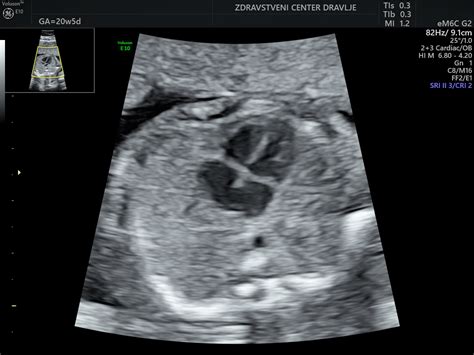

Asimetrija možganov pomeni, da leva in desna polovica možganov nista povsem enako veliki ali enako razviti. To je lahko posledica različnih dejavnikov, ki vplivajo na razvoj možganov med nosečnostjo ali po rojstvu. Pomembno je poudariti, da na ultrazvoku NIKAKOR NE VIDI OTROKOVE INTELIGENTNOSTI. Ultrazvok lahko prikaže strukturne nepravilnosti ali odstopanja v razvoju organov, vendar ne more natančno napovedati kognitivnih sposobnosti otroka. Zdravnik, ki je podal diagnozo, je morda opisal vse možne posledice ugotovljene asimetrije, vendar to ne pomeni, da se bodo te posledice nujno uresničile.

Vprašanje je tudi, kakšna je stopnja te asimetrije. Kot je bilo omenjeno, tudi pri popolnoma zdravih posameznikih leva in desna možganska hemisfera nista vedno popolnoma enaki. Ključnega pomena je celostni razvoj otroka. Če se dojenček sicer razvija normalno, kot v primeru, ko se je začel kotaliti pri 3,5 mesecih, 14 dni že samostojno sedi, reagira na okolico, se smeji, opazuje, poskuša komunicirati z različnimi zvoki in prijema igrače, so to vsekakor zelo dobri znaki.

Pomembno vprašanje je tudi, ali ima dojenček še vedno mehko lobanjsko "fontanelo" (mečavo). Če je ta še mehka, to pomeni, da se lobanjske kosti še niso povsem zrasle. Takrat je ultrazvok možen, kasneje pa se lahko za podrobnejše preiskave uporabi magnetna resonanca.